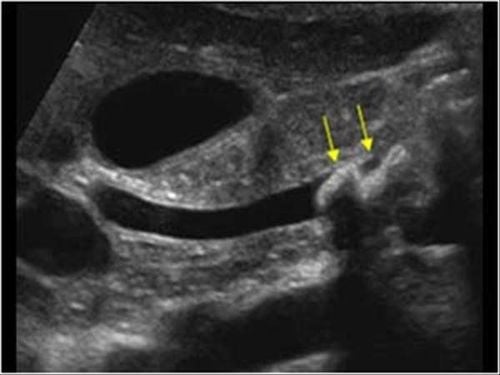

- Hình ảnh sỏi ống mật chủ trên siêu âm thường là cấu trúc tang âm kèm bóng cản và nằm trong ống mật chủ. Tương tự, sỏi túi mật sẽ thấy bóng cản đậm nằm trong túi mật.